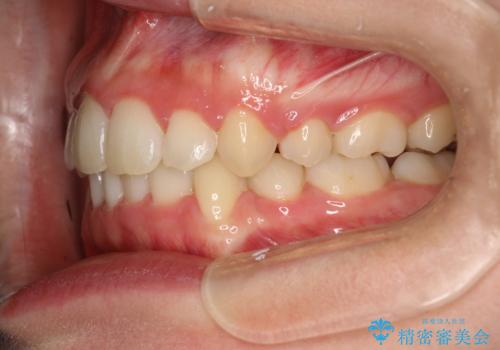

全体的ながたつき ワイヤーによる抜歯矯正で整った歯並びへ

- 上下の全体的ながたつきが気になるとのことで来院されました。

上下左右の前から4番目の歯を抜歯をして、ワイヤー矯正にて並べる計画としました。

患者様が装置を早期に除去したいという希望もあり、少々下の前歯のがたつきが残った状態で矯正を終了しました。

全体的ながたつきがなくなり、見た目の印象がよくなりました。